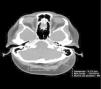

Se trata de una mujer española de 49 años, con antecedentes de psoriasis leve-moderada con afectación del cuero cabelludo y las uñas desde los 20 años, e intervenida de cáncer de mama (T3 N1 M0) 3 años antes; se encontraba en tratamiento habitual con tamoxifeno desde hacía 6 meses. Acude a nuestra consulta por intenso dolor y engrosamiento del cuero cabelludo de 3 meses de evolución, así como pérdida de pelo en la región occipital en las últimas semanas. La paciente había acudido 3 semanas antes al Servicio de Urgencias de nuestro Hospital por dolor intenso en el cuero cabelludo, donde le realizaron una tomografía computarizada (TC) en la que se puso de manifiesto una asimetría de volumen de partes blandas, a expensas de un engrosamiento importante del tejido subcutáneo en el vértex y en el área occipital izquierda que medía hasta 3,12cm (fig. 1).